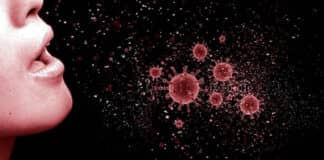

Ετικέτα: ΚΡΟΥΣΜΑΤΑ

Κορωνοϊός: 698 κρούσματα, 328 στην Αττική, (28 στην Ανατολική), 26 θάνατοι,...

Σε 698 ανέρχονται τα νέα κρούσματα κορωνοϊού στη χώρα το τελευταίο 24ωρο, σύμφωνα με την ενημέρωση του ΕΟΔΥ.

Κατά το ίδιο διάστημα,...

Κορωνοϊός: 662 κρούσματα, 332 στην Αττική, (48 στην Ανατολική), 23 θάνατοι,...

Σε 662 ανέρχονται τα νέα κρούσματα κορωνοϊού το τελευταίο 24ωρο, σύμφωνα με τον Εθνικό Οργανισμό Δημόσιας Υγείας (ΕΟΔΥ). Το ίδιο διάστημα κατεγράφησαν 23 θάνατοι....

Κορωνοϊός: 1.222 κρούσματα, 583 στην Αττική, (78 στην Ανατολική), 26 νεκροί,...

Σταθερή είναι η επιβάρυνση του επιδημιολογικού φορτίου σε ολόκληρη τη χώρα, γεγονός που έφερε νέα πιο σκληρά μέτρα τύπου Αττικής σε Αχαΐα και Εύβοια....

Κορωνοϊός: 1.410 κρούσματα, 762 στην Αττική, (66 στην Ανατολική), 21 θάνατοι,...

Σε 1.410 ανέρχονται τα νέα κρούσματα κορωνοϊού στη χώρα το τελευταίο 24ωρο, σύμφωνα με την ενημέρωση του ΕΟΔΥ, ενώ 762 εξ αυτών εντοπίζονται στην...

Κορωνοϊός: 1.327 κρούσματα, 676 στην Αττική, (78 στην Ανατολική), 22 θάνατοι,...

Λιγότερα από χθες, αλλά σταθερά σε υψηλά επίπεδα παραμένουν τα περιστατικά σε Αττική και Αχαΐα, ενώ αύξηση σημειώνεται στη Θεσσαλονίκη.

Κορωνοϊός: 1.496 κρούσματα, 795 στην Αττική, (76 στην Ανατολική), 17 θάνατοι,...

Σε 1.496 ανέρχονται τα νέα κρούσματα κορωνοϊού που κατεγράφησαν το τελευταίο 24ωρο, όπως ανακοίνωσε ο Εθνικός Οργανισμός Δημόσιας Υγείας (ΕΟΔΥ).

Δυσοίωνο, λόγω μεταλλάξεων το μέλλον της πανδημίας. Κατά 35% με πολύ...

Ιδιαιτέρως ανησυχητικά είναι τα νέα σχετικά με τις μεταλλάξεις του κορωνοϊού, που διαρκώς πληθαίνουν.

Κορωνοϊός: 1.526 κρούσματα, 750 στην Αττική, (84 στην Ανατολική), 20 θάνατοι,...

Σε 1.526 ανέρχονται τα νέα κρούσματα κορωνοϊού σήμερα, Τρίτη, 9 Φεβρουαρίου 2021, σύμφωνα με την ανακοίνωση του Εθνικού Οργανισμού Δημόσιας Υγείας (ΕΟΔΥ), με τα...

Κορωνοϊός: 638 κρούσματα, 321 στην Αττική, (44 στην Ανατολική), 25 θάνατοι,...

Νέα μικρή αύξηση καταγράφεται και σήμερα στον αριθμό των διασωληνωμένων ασθενών με κορωνοϊό, σύμφωνα με τα στοιχεία που έδωσε στη δημοσιότητα ο ΕΟΔΥ, παρά...

Κορωνοϊός: 733 κρούσματα, 360 στην Αττική, (29 στην Ανατολική), 21...

Μετά από πέντε 24ωρα συνεχούς καταγραφής τετραψήφιου αριθμού κρουσμάτων ανά ημέρα, ο Εθνικός Οργανισμός Δημόσιας Υγείας (ΕΟΔΥ) ανακοίνωσε 733 νέες μολύνσεις του κορωνοϊού. Το...